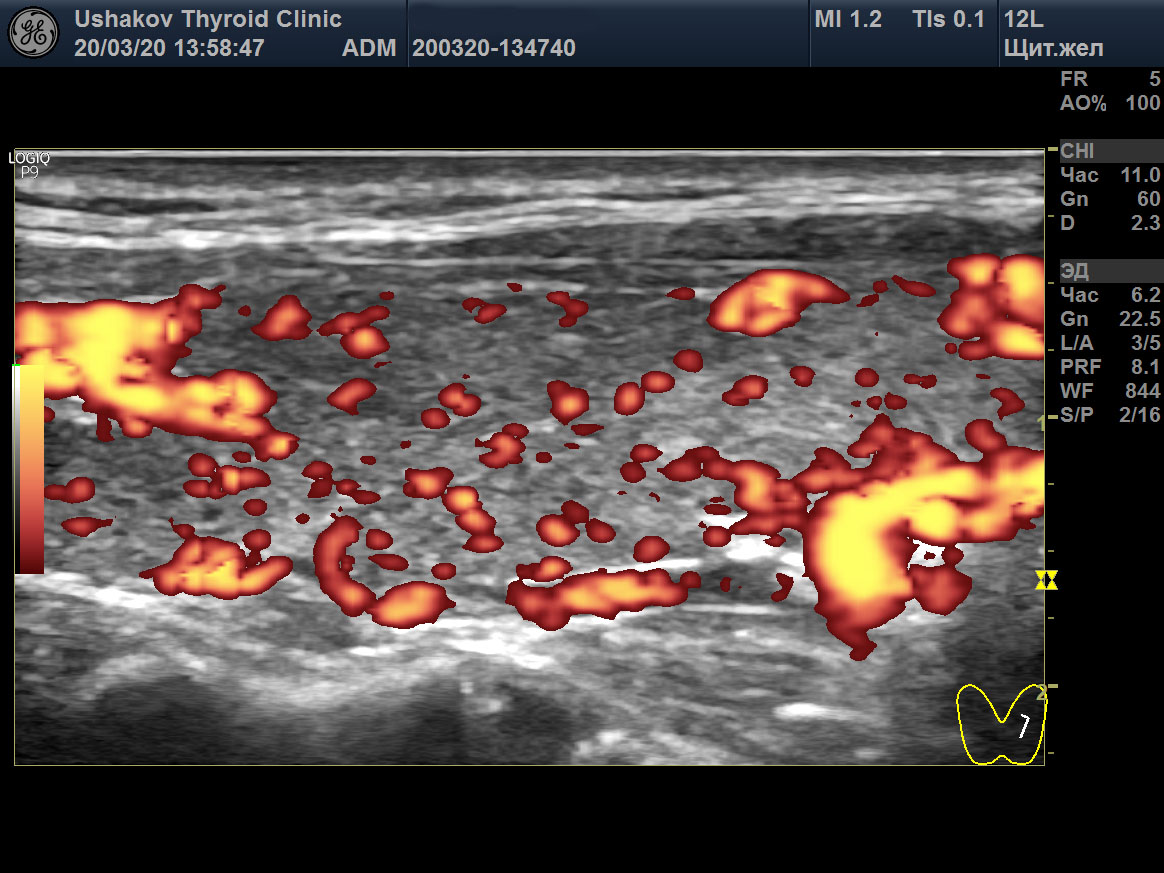

Пример такого случая представлен на

снимках ниже, где показаны две доли ЩЖ пациентки 31 года в режиме ЭДК и ПССК в системе верхних щитовидных артерий (ВЩА). Интенсивность кровотока при ЭДК усилена до значительной степени, а ПССК – до умеренно избыточной величины (норма 20-30 см/с [127]).

Рисунок 1 Левая и правая доли ЩЖ пациентки 31 года (поперечные и продольные проекции в режиме ЭДК; ПССК в режиме ЦДК), УЗИ 20.03.2020. Объём ЩЖ 9,1 мл (рост 170 см, масса 50 кг). Данные анализа крови от 18.03.2020: ТТГ 33,6 мЕд/л [0,4-4,0], Т4св. 6,7 пмоль/л [9,0-19,0], Т3св. 4,1 пмоль/л [3,0-5,6], АТТПО >1000 Ед/мл [<5,6], АТ-ТГ 368,8 Ед/мл [<18]. ПССК в системе ВЩА слева и справа 54 см/с. Концентрация йода в моче 200 мкг/л. Медикаменты не принимает продолжительный период.

Рисунок 1 продолжение

Рисунок 1 окончание |

В результате при обращении в нашу Клинику были выявлены признаки значительного перенапряжения ЩЖ по данным УЗИ в виде значительной интенсификации тиреоидного кровотока (

рис. 1). Эта избыточная стимуляция ЩЖ со стороны гипофиза (ТТГ 33,6 мЕд/) и периферической ВНС, тем не менее, сопровождалась